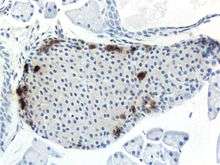

Mouse islet immunostained for pancreatic polypeptide